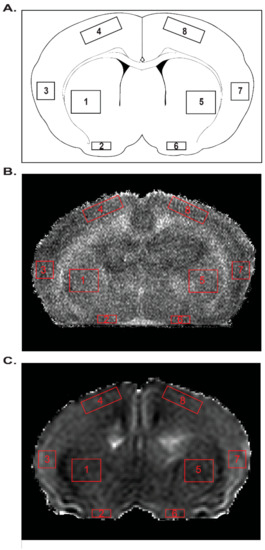

2.6. MRI

4.8. Neurobehavior